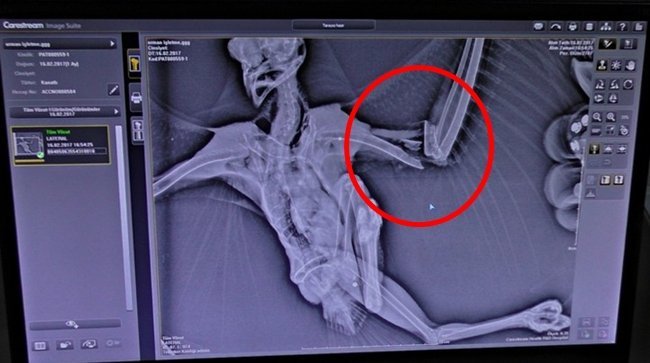

Veteriner hekim Tolga Kandıralı yaptığı açıklamada, yaralı şahinin röntgen filminin çekildiğini, vücudunda saçma ve kanadında kırık tespit ettiklerini söyledi. Yaralı şahinin kanadına anestezi altında pim uygulaması yaptığını belirten Kandıralı, operasyonun başarılı geçtiğini ve 3 gün bakımları yapıldıktan sonra Gökçebey’de bulunan hayvanat bahçesine teslim edileceğini söyledi.